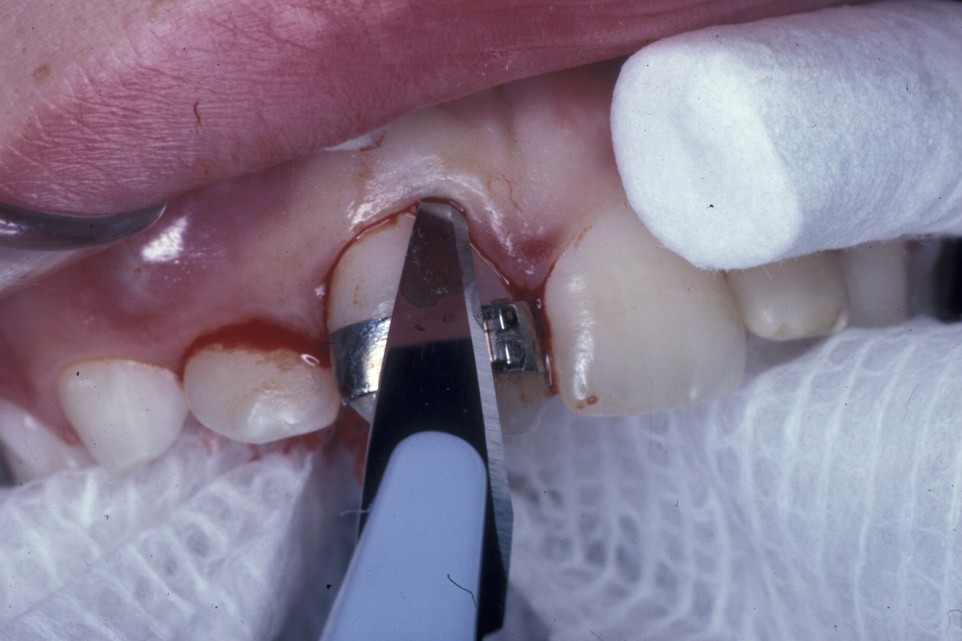

Surgery involves the same access as for the removal of the tooth, except that great care must be taken not to damage the cementum of the root surface as this can lead to ankylosis of the tooth and subsequent failure of eruption. An adequate amount of the crown should be exposed to allow attachment of the bracket and chain. Prior to bonding the bracket to the tooth, the area should be as uncontaminated as possible. Bleeding should be arrested as much as practicable with the use of local application of vasoconstrictors (as is added to some local anaesthetics) or the use of diathermy. Once the area is prepared, the tooth surface should be washed with saline or water and then prepared for bonding either with acid etch or with self-etch priming agents. The latter offer the advantage that they do not need to be rinsed off, need less time to prepare the tooth and are to some extent hydrophilic.